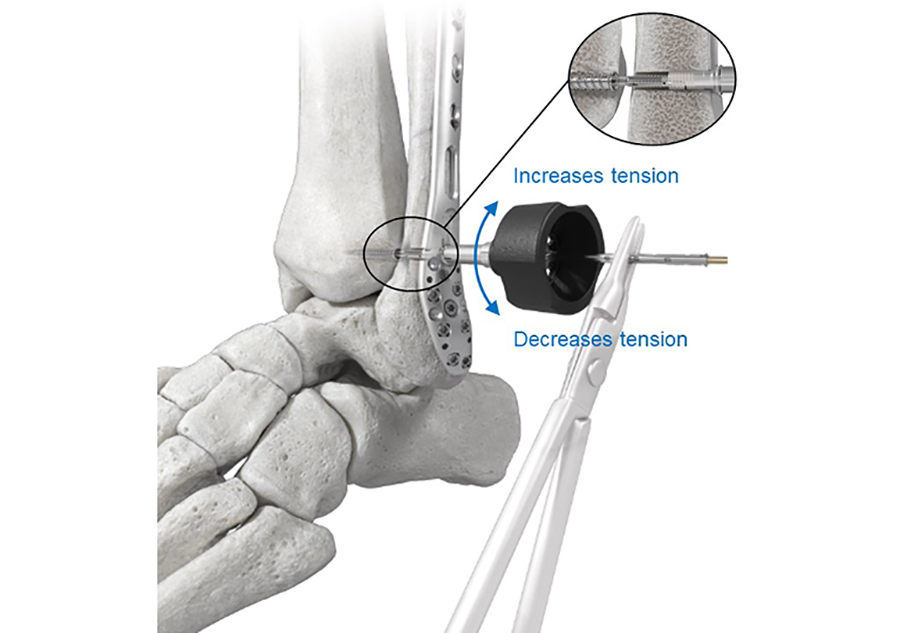

The Tensioning Knob is used to fine tune and readjust the tension in the Suture Bridge intraoperatively (Fig 3). Clockwise or counterclockwise rotation of the Tensioning Knob will advance or reverse the Fibula Tensioning Cap, thereby adjusting the tension in the suture bridge in a two-way tension control to achieve the desired level of correction.

The FIBULINK fixation concept does not require medial soft-tissue disruption and helps improve procedural efficiency by delivering fixation through a single lateral incision. Since it does not rely on hardware placement on the medial tibia it eliminates medial side complications, such as damage to neurovascular structures and soft-tissue entrapment associated with suture button constructs. It also limits interference with the placement of additional hardware on the medial side (eg, medial malleolar screws), which might be required because of the injury (eg, high-energy injury).